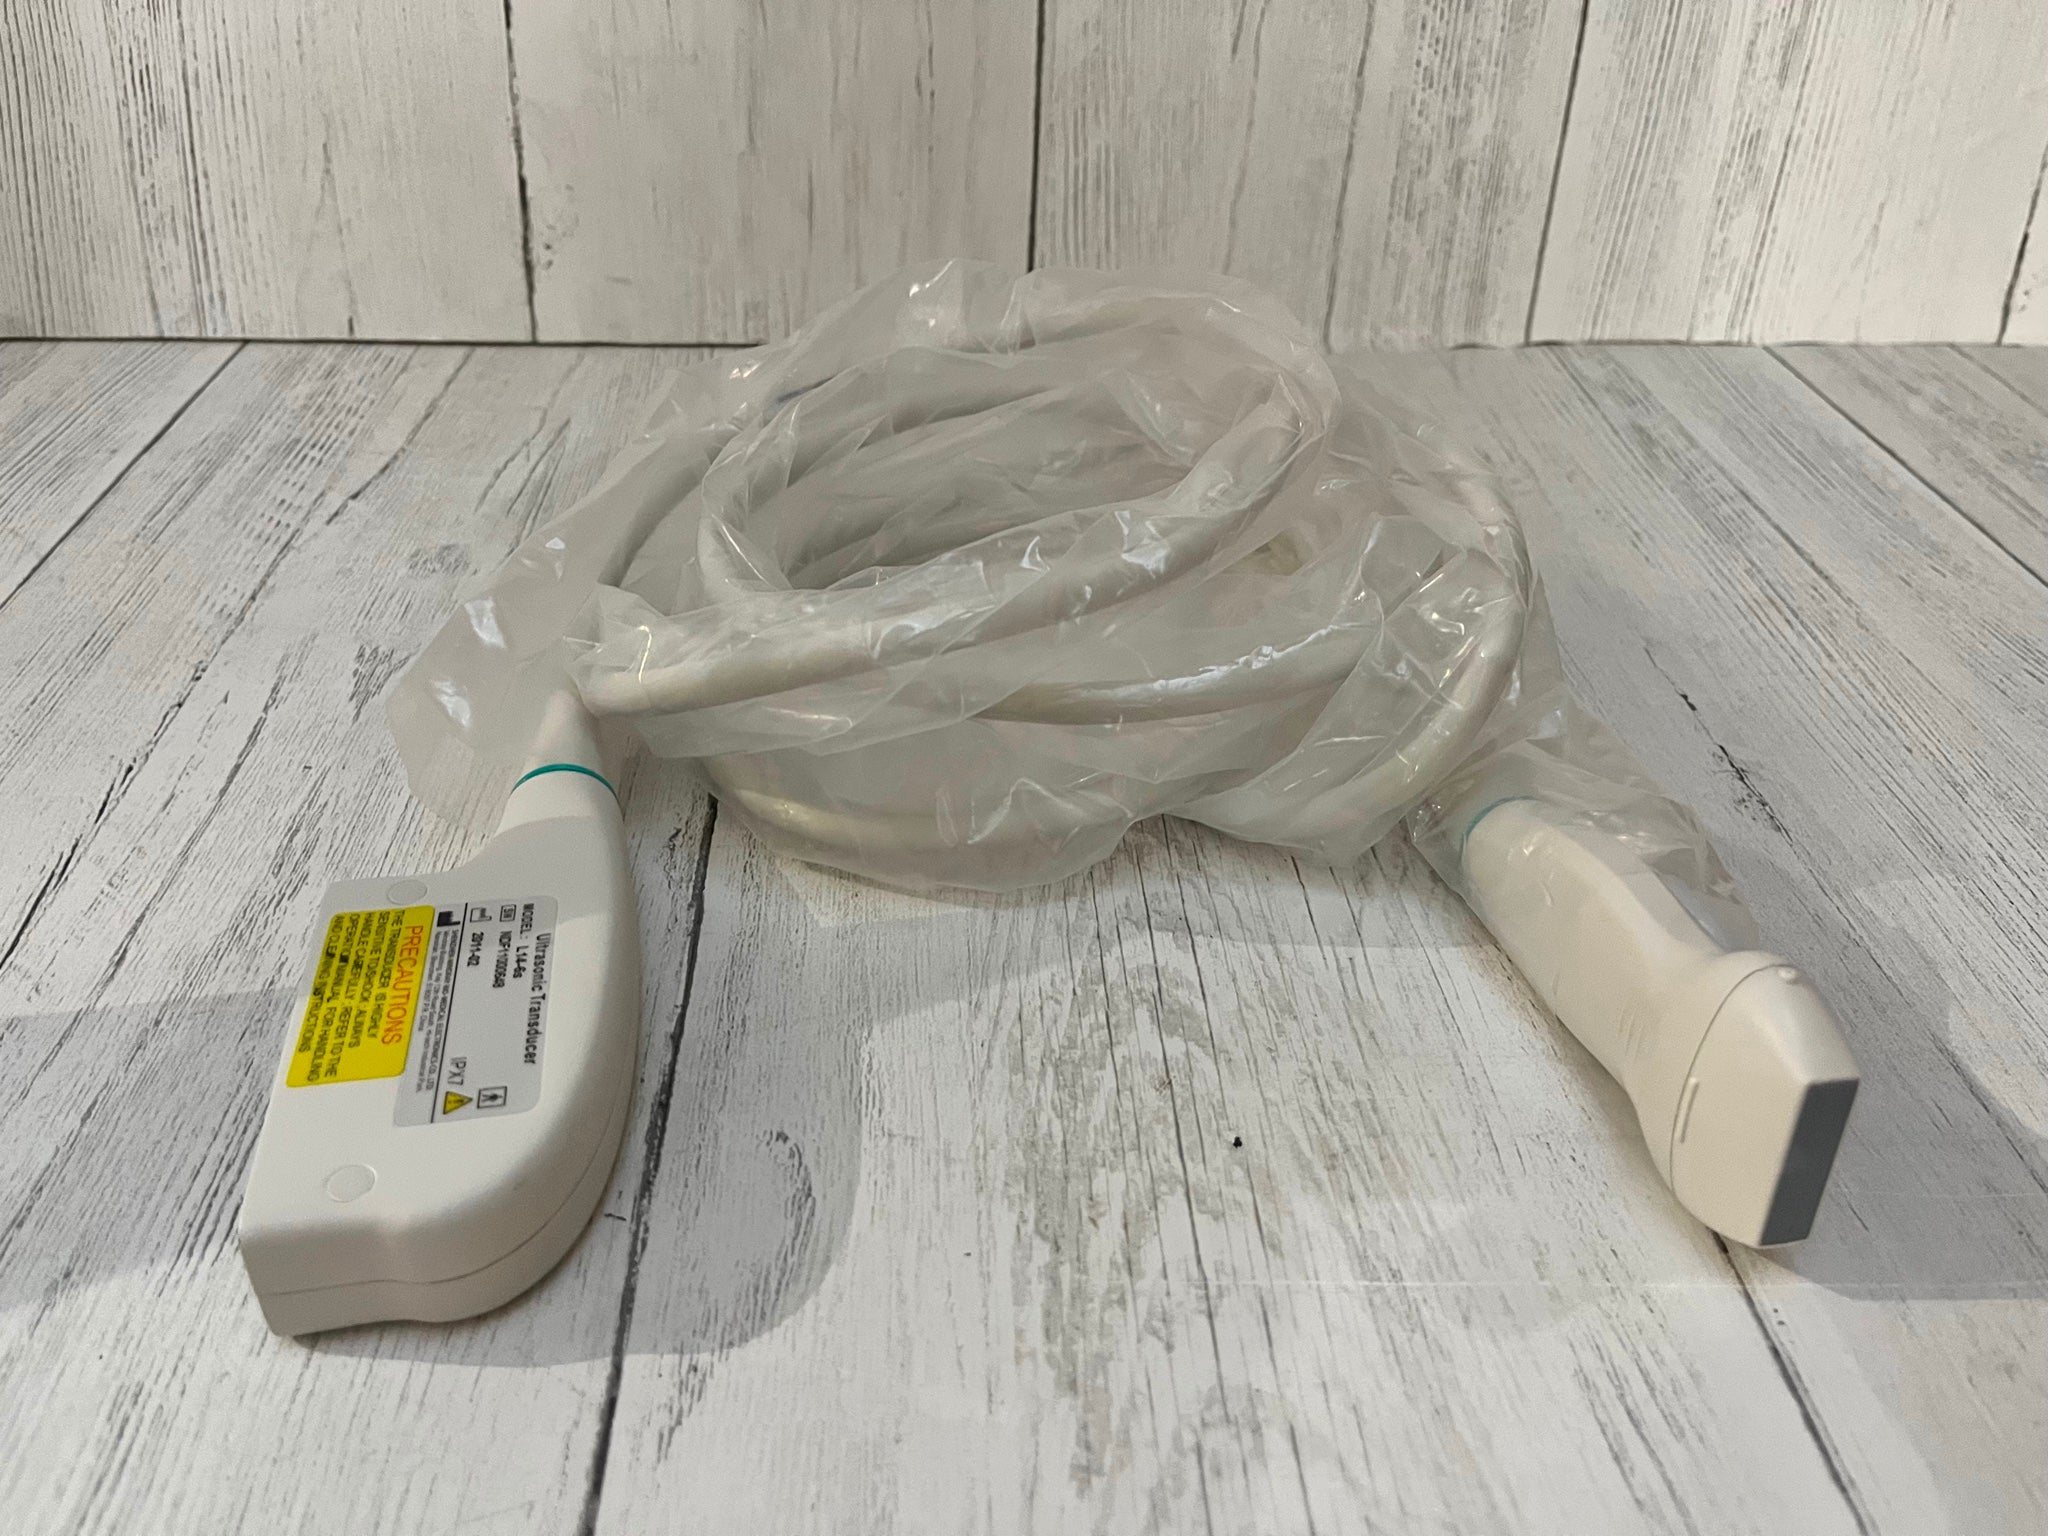

Probe Function: 3.5MHZ convex, abdominal organs

Probe 2: 7.5MHZ Transvaginal probe:gynecologic examination

The Diagnostic Ultrasound Scanner stands out for its exceptional imaging capabilities. Utilizing advanced digital technology, it provides clear and precise images, essential for accurate diagnostics. This scanner is equipped with both convex and transvaginal probes, allowing healthcare professionals to perform a wide range of examinations. Because of this versatile functionality, it greatly enhances the diagnostic process in various medical fields.